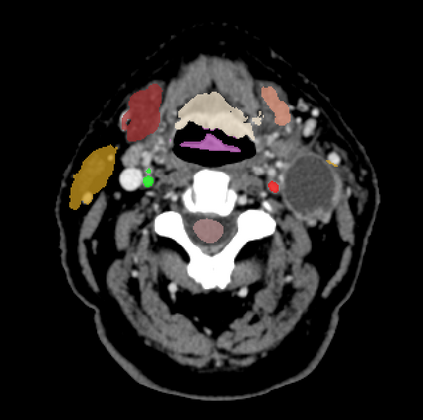

Organ at risk (OAR) segmentation is a critical process in radiotherapy treatment planning such as head and neck tumors. Nevertheless, in clinical practice, radiation oncologists predominantly perform OAR segmentations manually on CT scans. This manual process is highly time-consuming and expensive, limiting the number of patients who can receive timely radiotherapy. Additionally, CT scans offer lower soft-tissue contrast compared to MRI. Despite MRI providing superior soft-tissue visualization, its time-consuming nature makes it infeasible for real-time treatment planning. To address these challenges, we propose a method called SegReg, which utilizes Elastic Symmetric Normalization for registering MRI to perform OAR segmentation. SegReg outperforms the CT-only baseline by 16.78% in mDSC and 18.77% in mIoU, showing that it effectively combines the geometric accuracy of CT with the superior soft-tissue contrast of MRI, making accurate automated OAR segmentation for clinical practice become possible. See project website https://steve-zeyu-zhang.github.io/SegReg